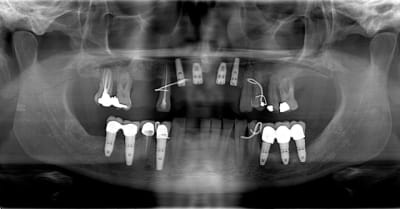

1 première consultation (septembre 2012)

2 rétro-alvéolaire (septembre 2012)

un an après !

ça s'arrange pas, voyez plutôt..

augmentation de la perte osseuse +++